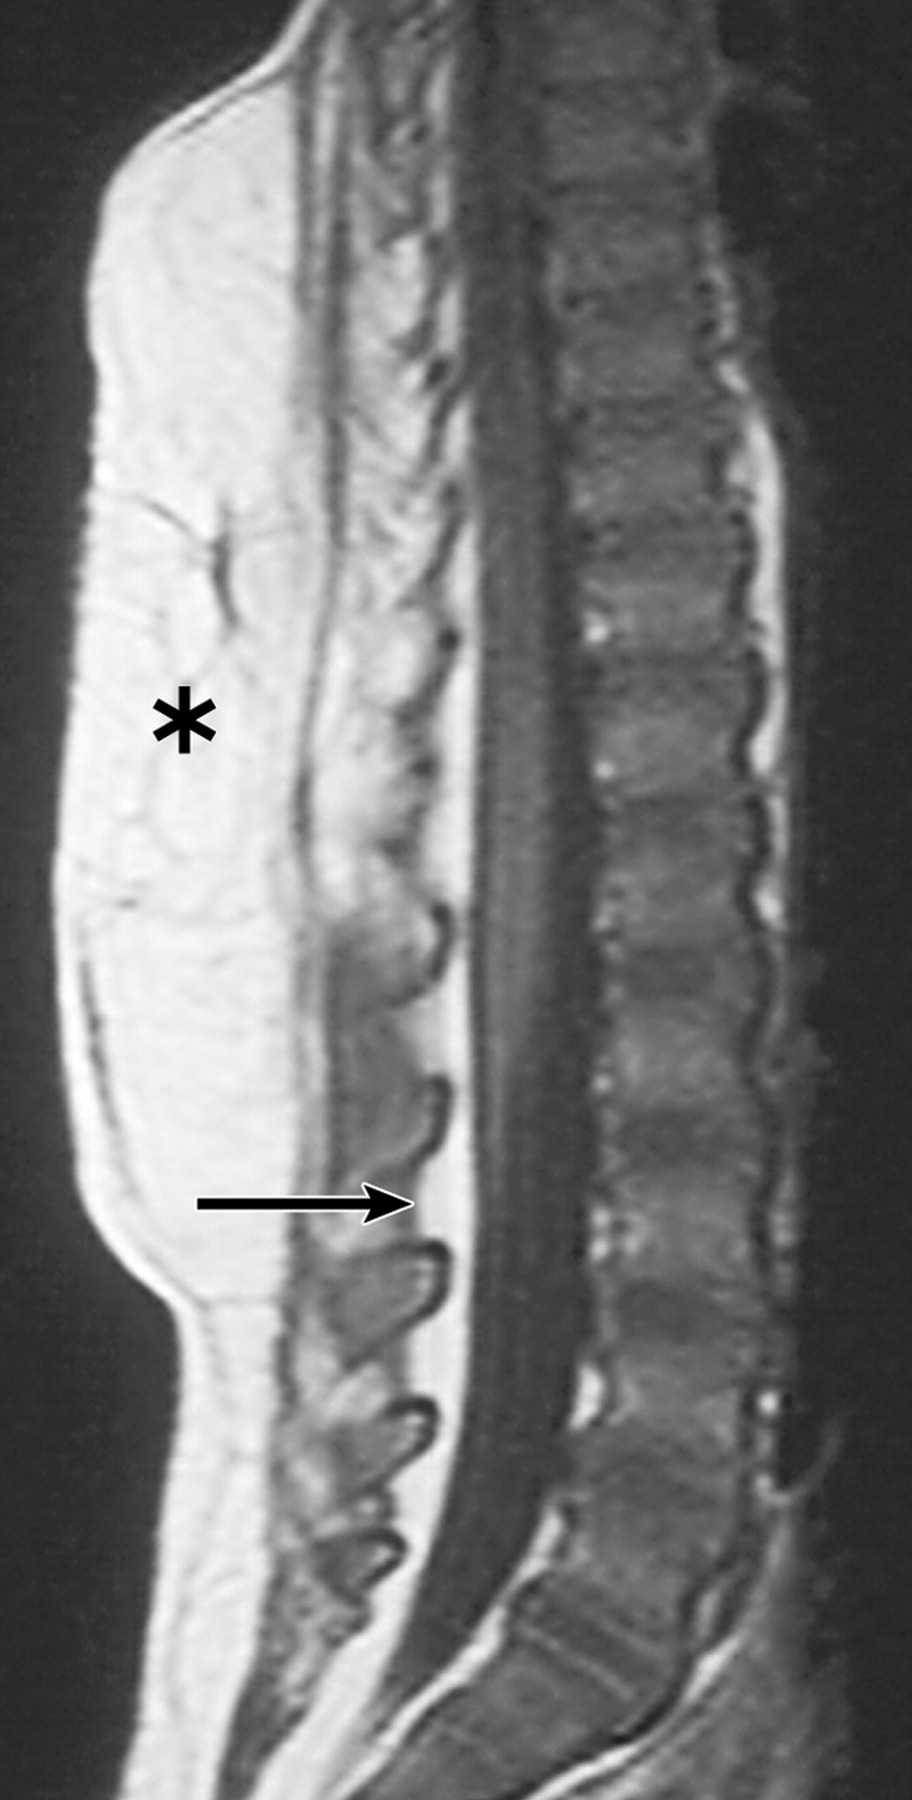

Клинические проявления заболевания характеризуются выраженным полиморфизмом. Наряду с типичной симптоматикой - парциальным гигантизмом рук и ног, гемигипертрофией, артериовенозными аномалиями, макроцефалией - наблюдаются разнообразные опухоли: бородавчатый эпидермальный невус, гемангиомы, лимфангиомы, липомы, гамартомы. Иногда отмечаются косоглазие, экзофтальм, миопия, прогения, варикозное расширение вен, разрастание кожи на подошвах. Примерно в 55% случаев выявляется умственная отсталость, в 13% - судорожный синдром. Наблюдались также больные с изолированной макродактилией, спленомегалией, избирательной патологией глаз и черепа в виде множественных менингиом, полимикрогирии, ретинальной пигментной дегенерации и атрофии зрительного нерва. Продолжительность жизни пробандов, как правило, невелика и колеблется от 3 до 40 лет. Смерть наступает чаще от злокачественных новообразований. Описаны такие опасные для жизни осложнения, как венозные тромбозы и эмболия легочной артерии. Так, A. Stavotinek и соавт. в 2000 г. сообщили о 3 больных, умерших в возрасте 12, 17 и 25 лет от эмболии легочной артерии [9].